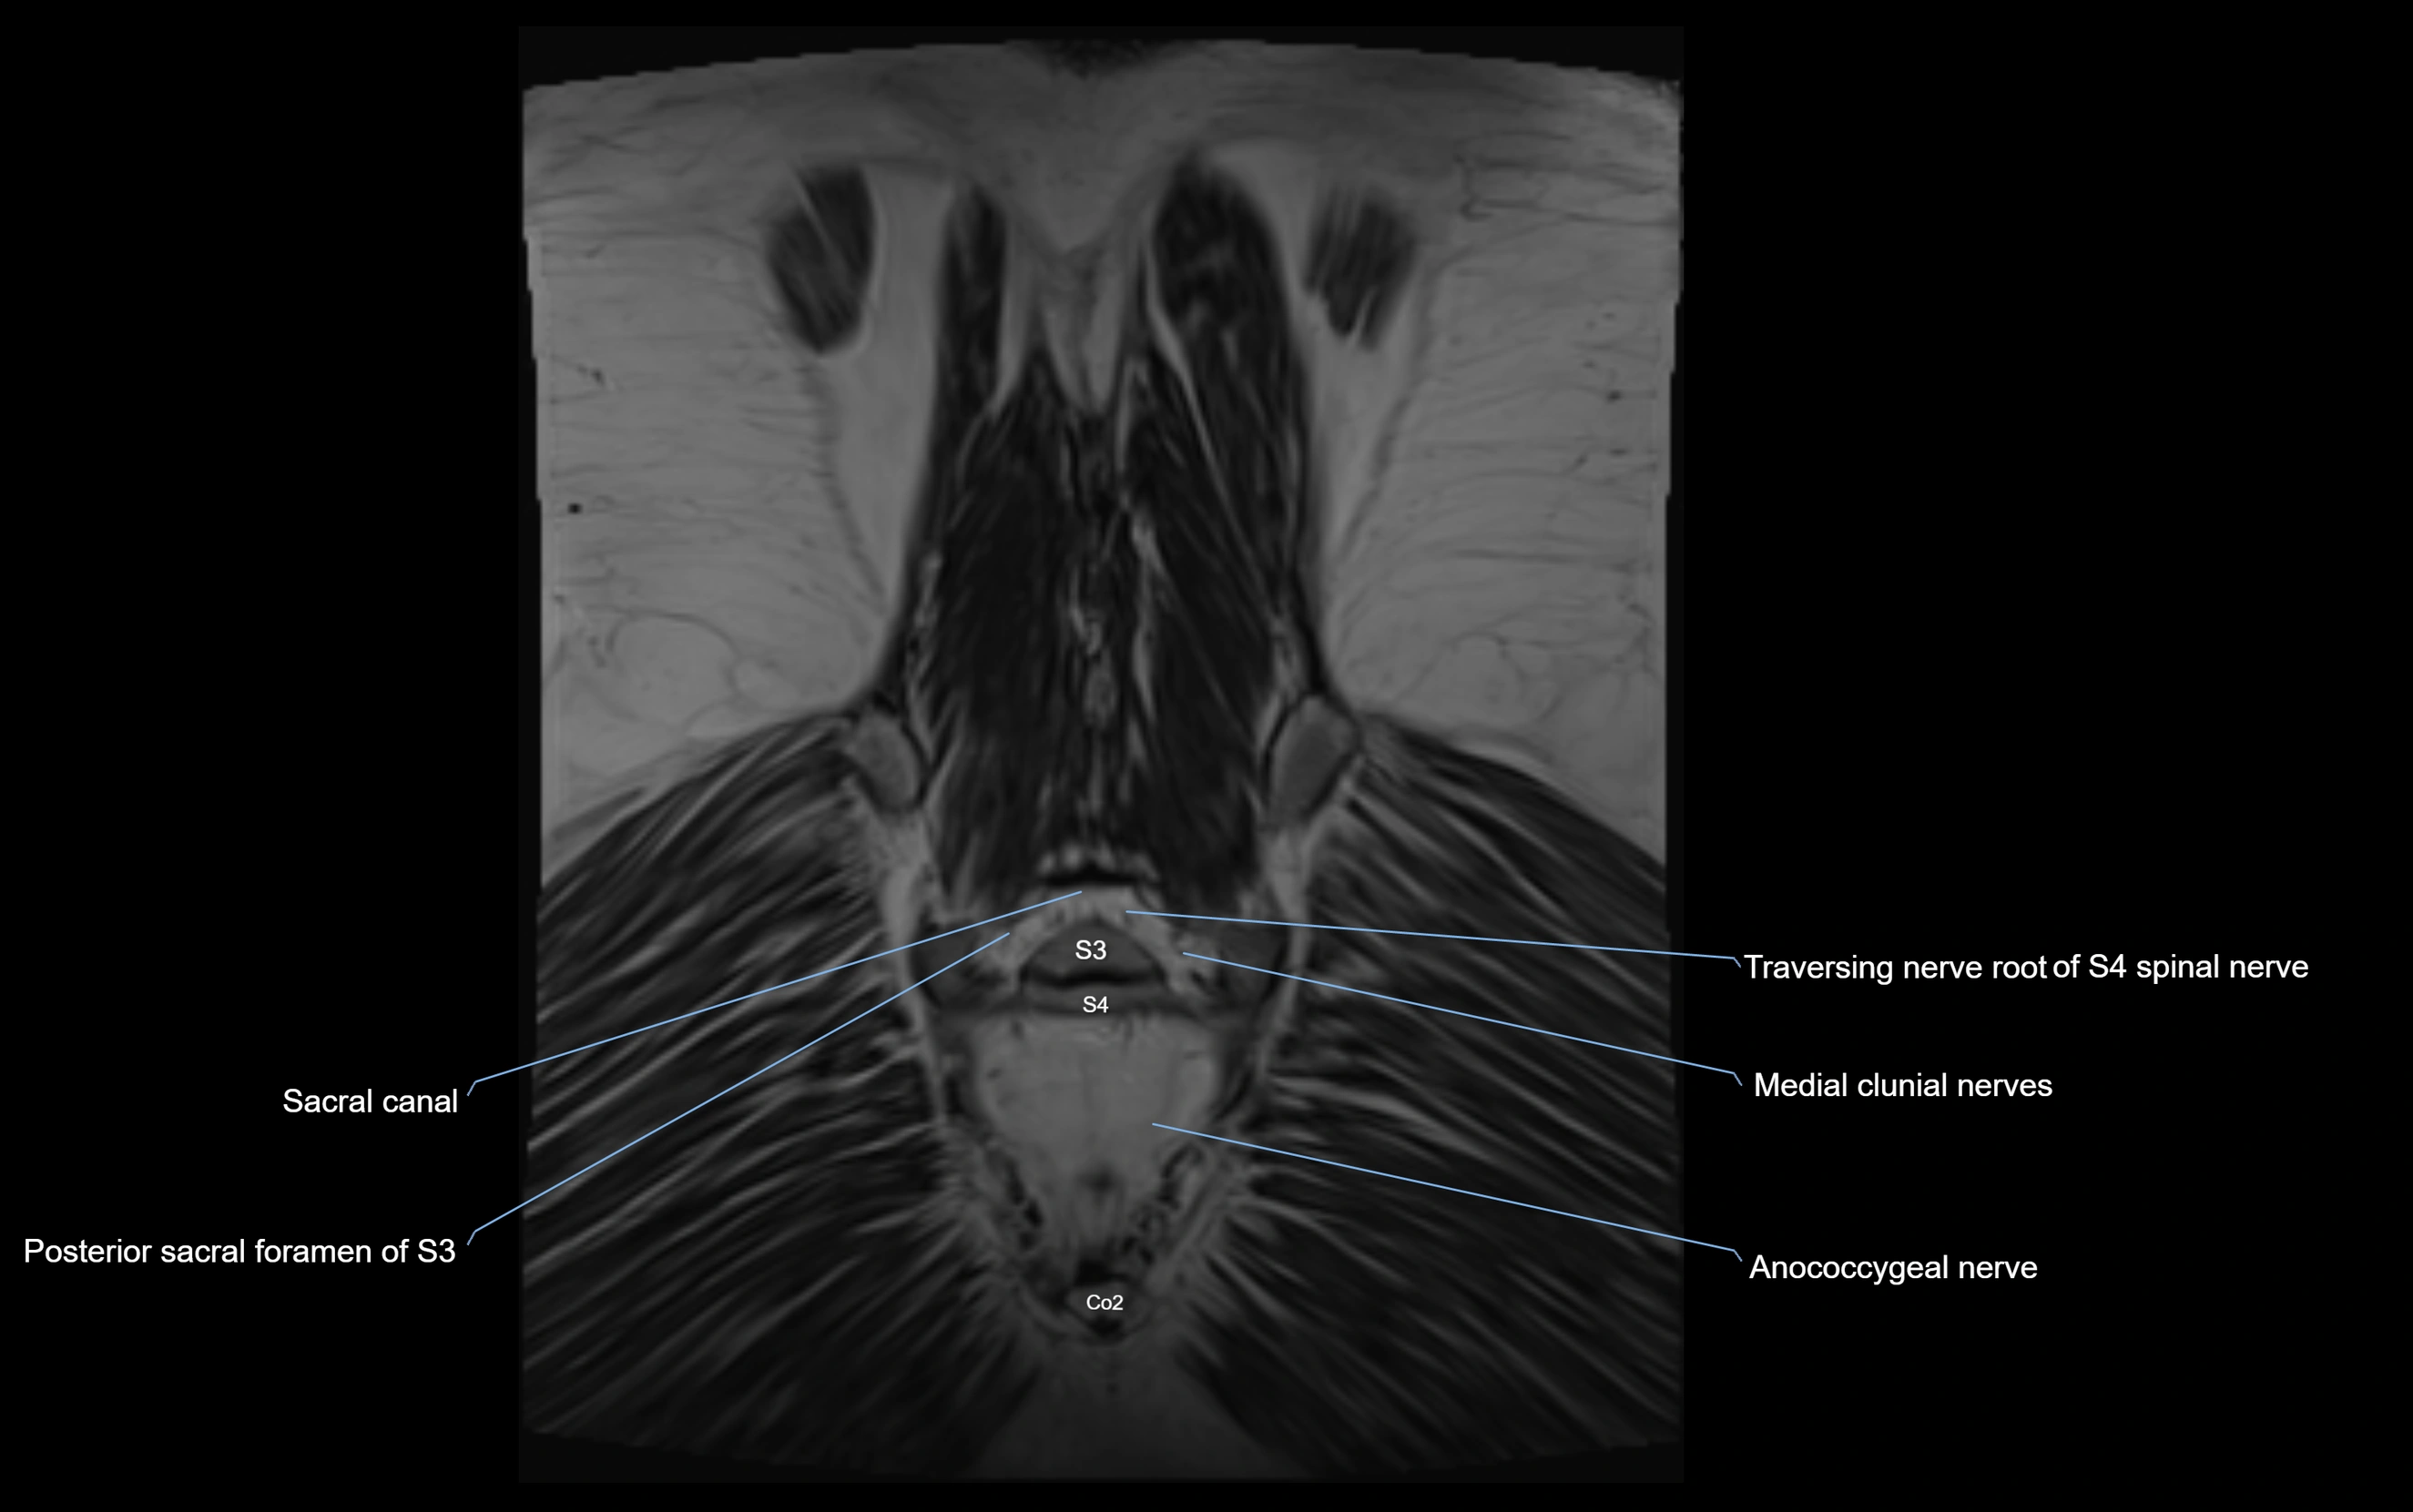

MRI image

image